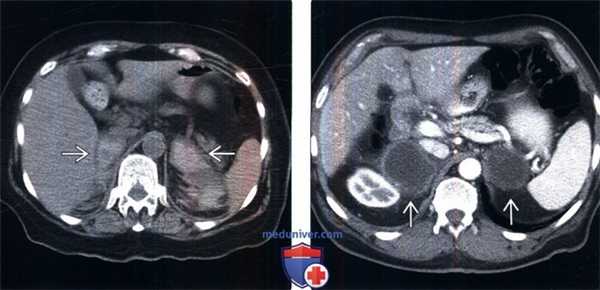

(Слева) У пожилой женщины на бесконтрастной КТ, выполненной для поиска причин артериальной гипотензии, гипонатриемии, гипогликемии и сепсиса, развившихся после артропластики коленного сустава, выявлено двустороннее кровоизлияние в надпочечники, что служит редкой причиной острой надпочечниковой недостаточности.

(Справа) У пожилого мужчины с раком легкого на КТ с контрастным усилением выявлены крупные некротизированные метастазы в надпочечниках. Данные лабораторных исследований (снижение уровня Na, повышение уровня К) и тест с АКТГ -стимуляцией подтвердили выраженную надпочечниковую недостаточность, которая была купирована поддерживающей терапией глюкокортикоидами.